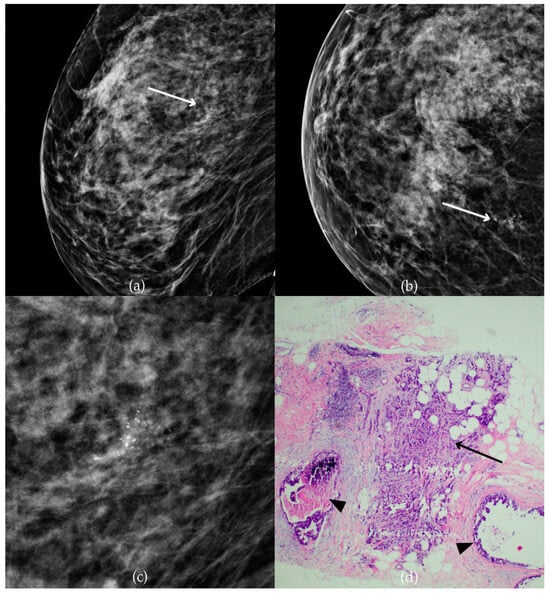

During a screening program, a 64-year-old patient presented with suspicious microcalcifications. The mammogram shown in Figure 3 of the patient’s right breast revealed a segmental distribution of coarse heterogeneous and fine pleomorphic calcifications in the upper outer quadrant, corresponding to a BI-RADS 4 finding. Tissue analysis obtained through VABB confirmed the presence of invasive carcinoma (category B5b). The patient underwent a mastectomy. Postoperative pathology showed only an in situ component, with no evidence of an invasive component, indicating that the invasive component was removed during the biopsy. One year after diagnosis, the follow-up US was reported as BI-RADS 2 classification, indicating benign imaging features.

Invasive breast cancer. (a) Mediolateral oblique (MLO) mammography view; (b) craniocaudal (CC) mammography view of the right breast showing coarse heterogeneous and fine pleomorphic calcifications (marked with arrows) in the upper outer quadrant, with segmental distribution. (c) Magnified mammographic image of coarse heterogeneous and fine pleomorphic calcifications with segmental distribution. (d) The histopathological image of the biopsy sample shows the characteristic features of invasive cancer (marked with arrow) and ductal carcinoma in situ (DCIS) (marked with arrowhead) (HE staining; 40× magnification).